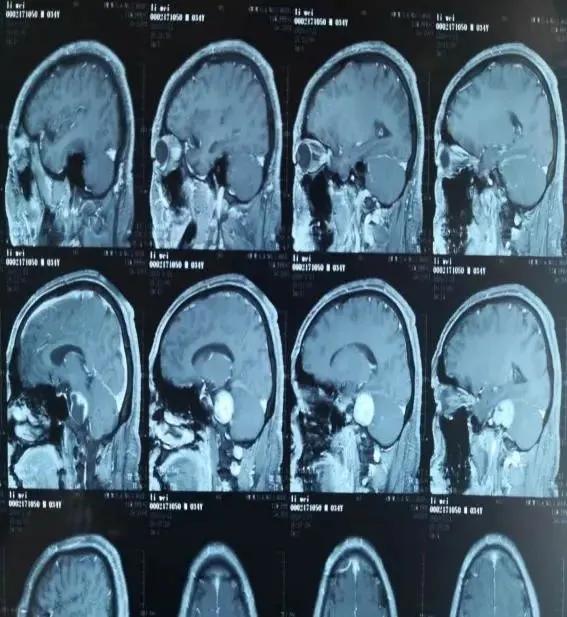

图一术前颅脑增强核磁扫描显示右侧桥小脑角区占位

随后,李先生来到云南省中医医院/云南中医药大学第一附属医院外科,入院后行颅脑核磁平扫+增强扫描提示:右侧内耳道扩大,其内可见一大小约3.8cm*3.5cm的囊实性结节影(图一)。